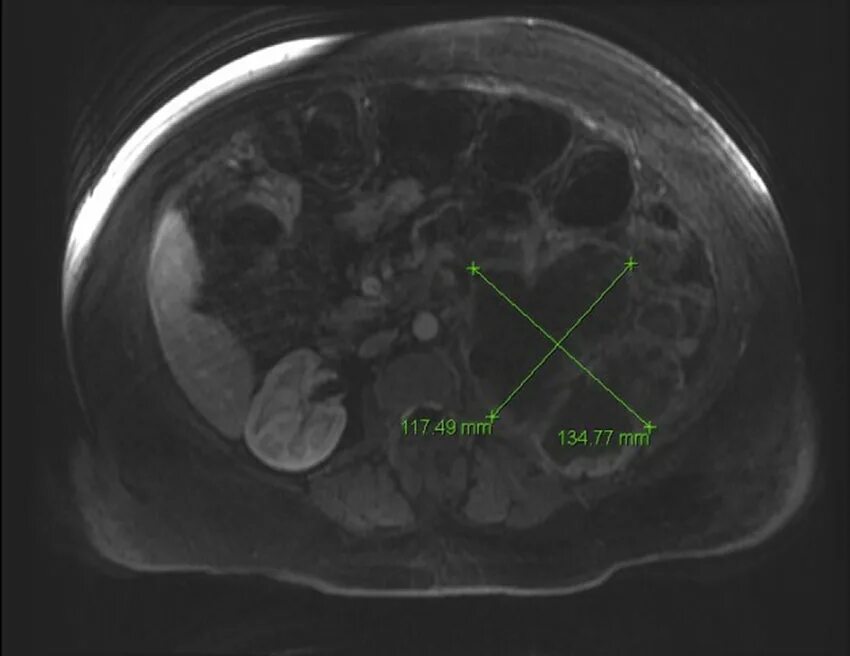

Метастазы рака почки